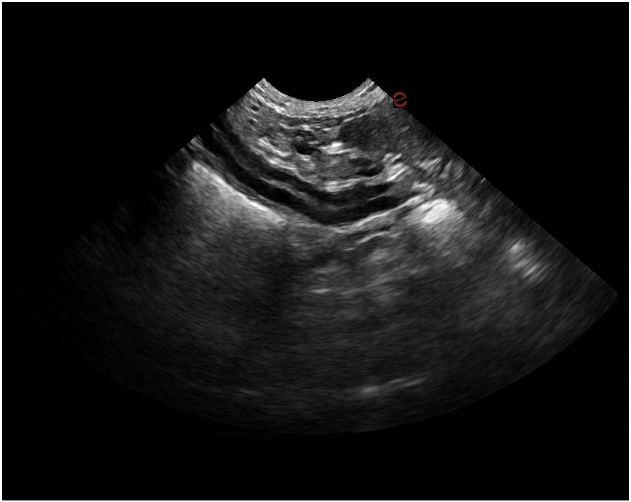

Esaote Q7 Vet er et trådløst, håndholdt ultralydapparat dedikert for veterinærer. Spesialtilpassete forhåndsinnstillinger og software og database designet for dyr. Esaote Q7 kombinerer kraften til moderne ultralydteknologi med brukervennlighet og mobilitet.

Med håndholdt ultralyd og en smartmobil/nettbrett, kan du gjøre raske og gode undersøkelser med Esaote Q7. Dets trådløse design gjør det mulig å utføre ultralydundersøkelser av høy kvalitet når som helst og hvor som helst. Alt er tilrettelagt for en vellykket undersøkelse.